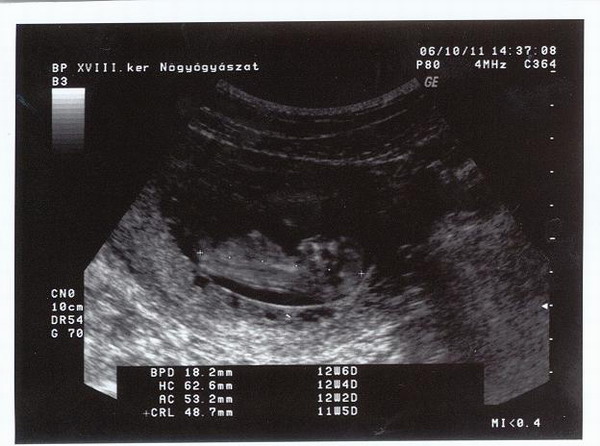

Orulok, hogy jol vagytok... Mi volt az uh-n? Nekem is hianyoznak a csevegesek, remelem hamarosan folyathatjuk!